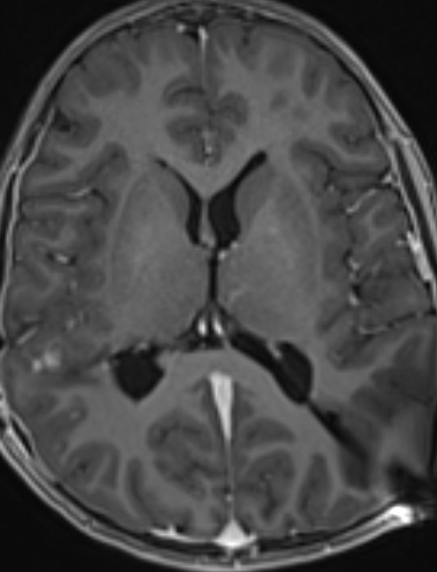

Please find below some images from the case:

OCT from early Jan 2026, when she first re-presented with vision loss in the left eye and disc edema. Very poor quality with poor fixation, but you can get a better sense of the left optic disc edema from the macular images.

Better quality OCT from the end of Jan after the shunt placement. The macular rasters don't catch the disc this time, so it's hard to compare, but I'd say the edema has clearly improved.

Post op MRI shows no significant change in the size of the ventricles, low lying cerebellar tonsils, similar to previous. Chiasm and nerves are small, unchanged from an MRI one year ago.